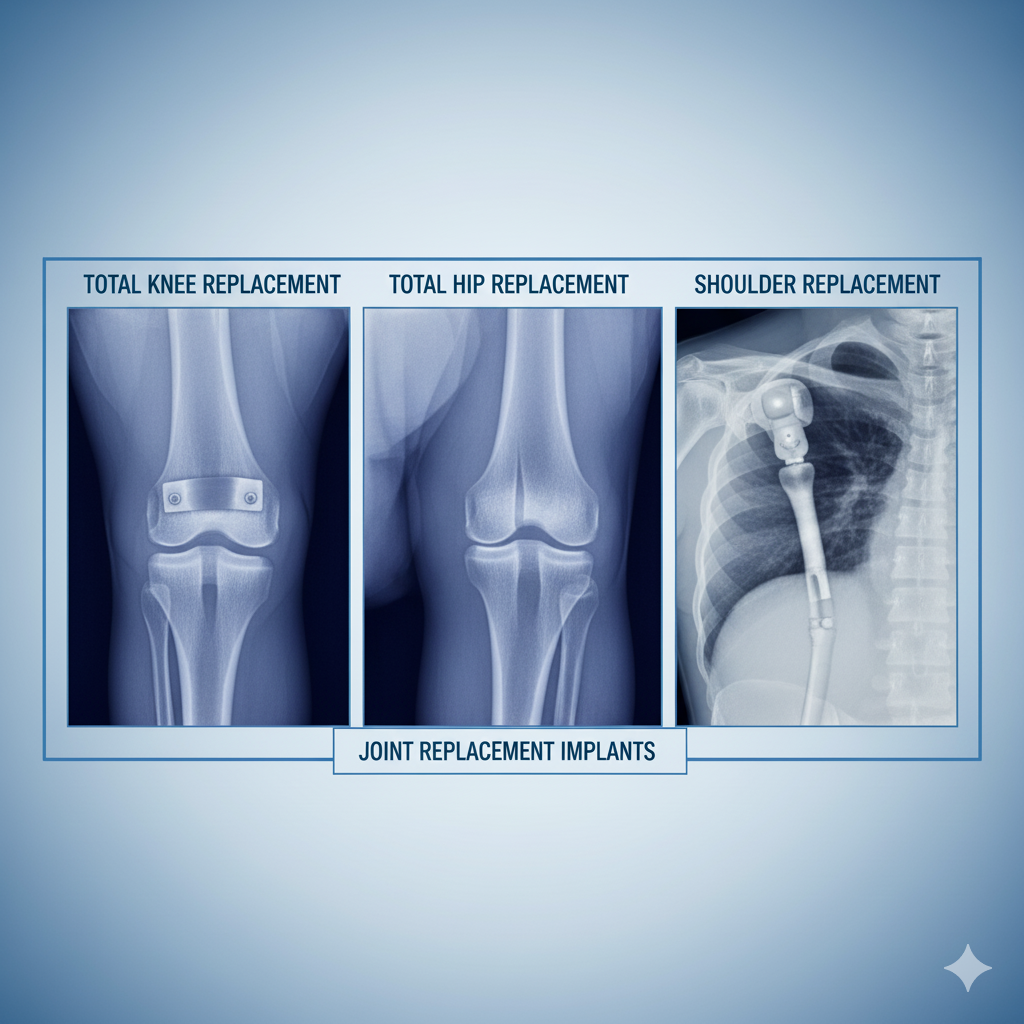

Best Joint Replacement Multi Specialist Hospitals in Kharkhoda Sonipat | Top Multi-Specialist Center for Joint Replacement in sonipat